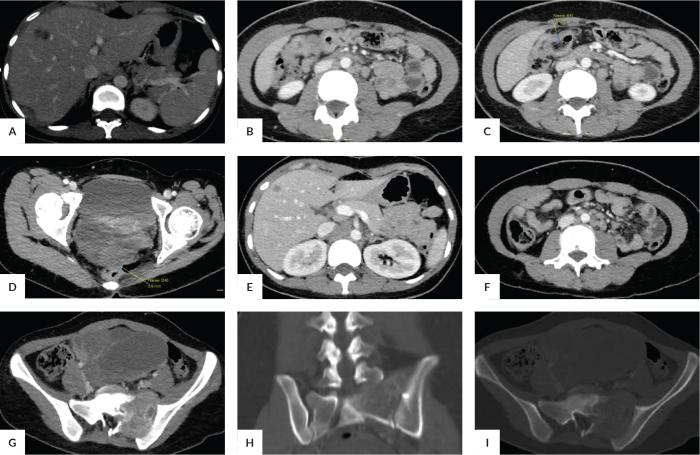

Krukenberg tumors are very rare. Its origin is difficult to define especially if its gross features mimic a primary ovarian cancer. We present a case of a 24-year-old Filipino female patient with metastatic mucinous ovarian adenocarcinoma of colonic origin that mimicked primary ovarian cancer and genitourinary tuberculosis. Surgery was done and histopathology revealed that the cancer was a metastatic mucinous adenocarcinoma of colonic origin. This case highlights the importance of differentiating between benign and malignant ovarian lesions as well as distinction between primary and metastatic ovarian neoplasms. Radiological imaging has an evolving role in diagnosis of different cancers, which may be improved through better clinical correlation and developing meaningful differential diagnosis while advancing to a more strategized algorithm in the diagnostic approach.

摘要